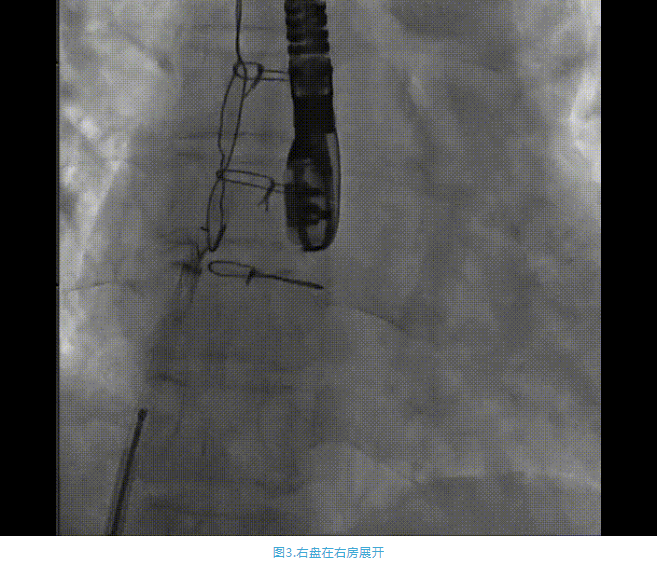

術(shù)中首先在局麻下穿刺股動脈、股靜脈,完成心導(dǎo)管檢查評估后轉(zhuǎn)為全麻,在食道超聲引導(dǎo)下穿刺房間隔,穿刺成功后將加硬導(dǎo)絲送入左上肺靜脈建立軌道,根據(jù)患者病情行球囊預(yù)擴張后植入6mm孔徑房間隔造孔支架,經(jīng)透視及食道超聲評估支架左右盤展開良好,夾持于房間隔兩側(cè),固定穩(wěn)定、位置良好,食道彩超顯示房水平右向左為主分流,分流孔直徑符合預(yù)期大小,心導(dǎo)管檢查評估達到預(yù)期效果,釋放造孔支架。術(shù)后12h患者下床活動,恢復(fù)順利,擬于近日完善術(shù)后評估后出院。